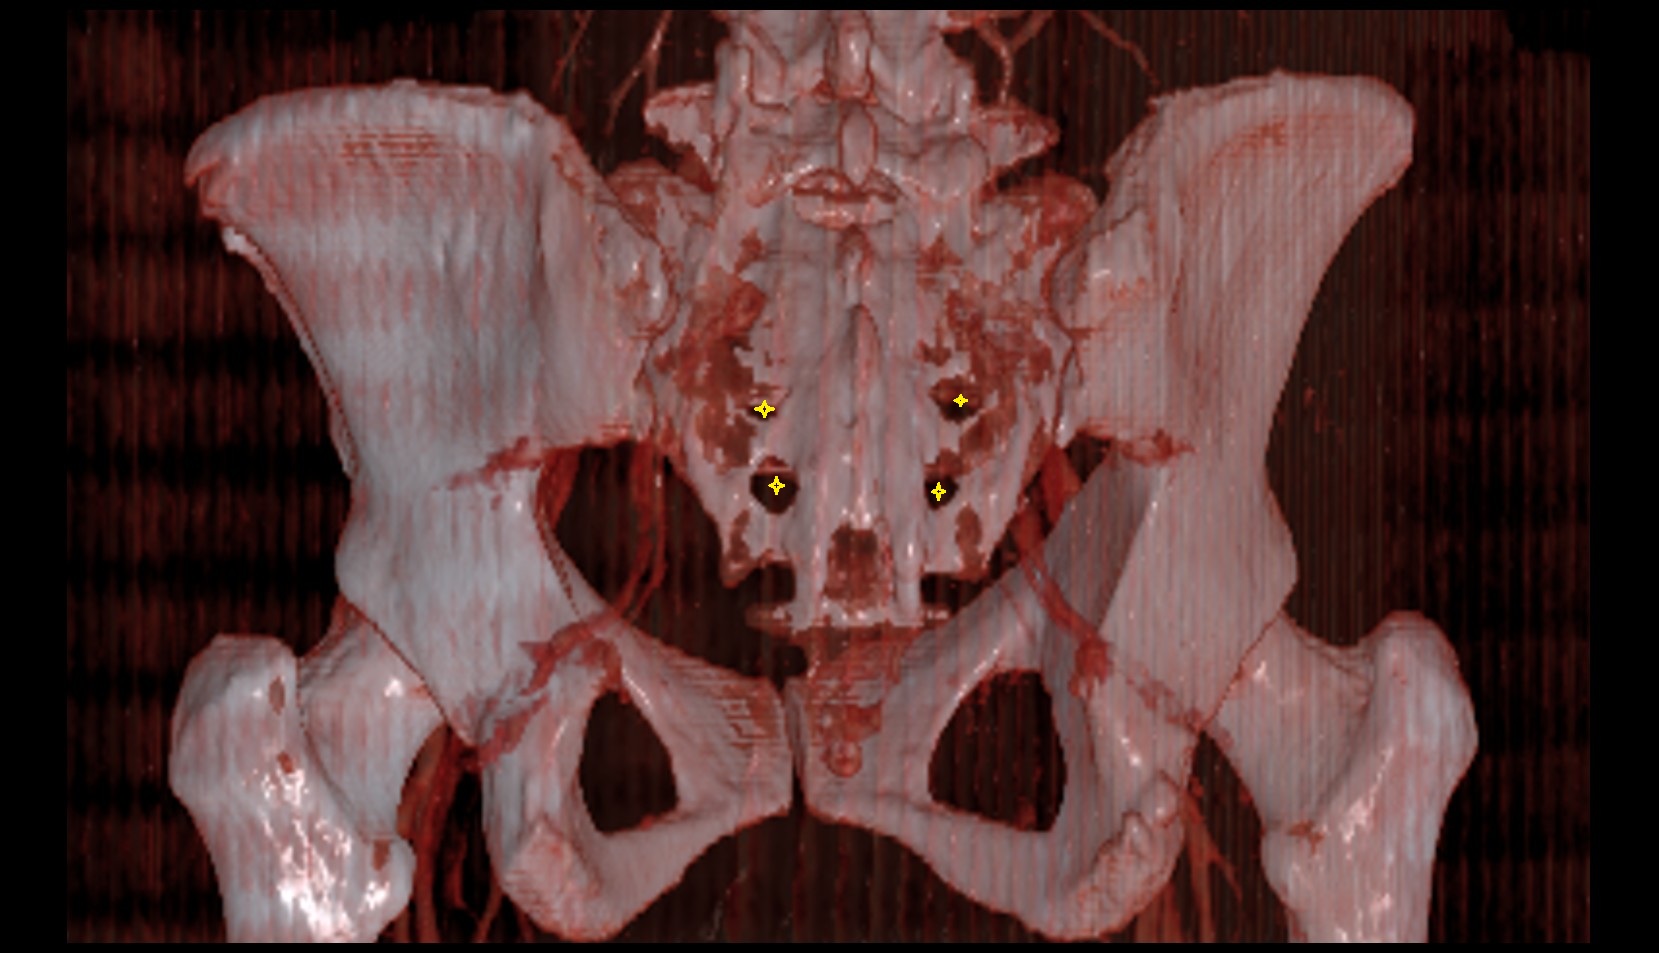

- Sacroiliac joint

- Anterior sacroiliac ligament

- Interosseous sacroiliac ligament

- Posterior sacroiliac ligament